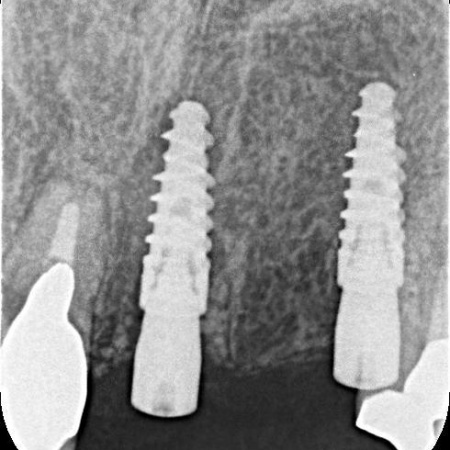

拝見したところ、欠損した左上前歯(側切歯)を補うために、両隣の歯を土台として人工歯を連結したブリッジが装着されていました。

しかし、レントゲン撮影をして詳しく検査を行うと、ブリッジの土台になっている2本の前歯(中切歯、犬歯)に虫歯が生じており、それにより歯がぐらぐらしていることが判明しました。

まず、左上前歯2本を唇側に健全な歯質をわずかに残しながら、慎重に抜きます。続いて、インプラントを適切な位置と角度で抜歯部位に埋入しました。

歯の一部(矢印部分)を残してインプラントを埋入